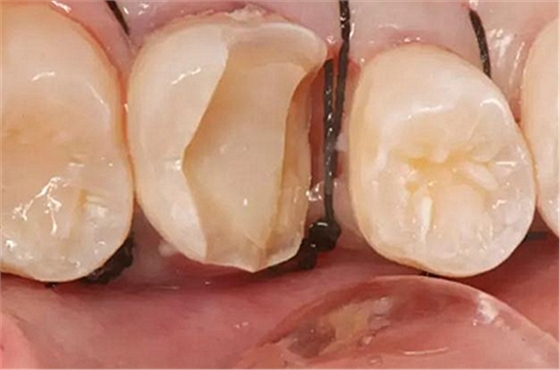

患者男性,35歲,B6銀汞充填后食物嵌塞,要求重新充填,口內(nèi)檢查見B6近中鄰頜面銀汞充填物,局部缺損,有繼發(fā)齲,去除原充填物及繼發(fā)齲,發(fā)現(xiàn)齲壞位于牙齦下方,給予冠延長手術(shù),同期嵌體預(yù)備,后一次性取模。(同樣設(shè)計(jì)為齦上邊緣)

硅橡膠取模后,灌注模型,科爾琥珀樹脂制作嵌體。